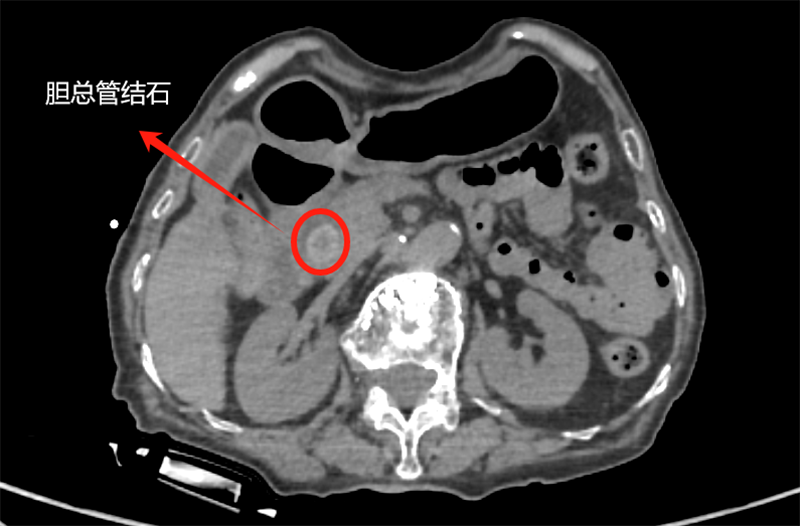

看著老人的狀態(tài)越來越差,家屬急得團團轉(zhuǎn),輾轉(zhuǎn)來到普外科。王龍華主任接診后,未沿用“腫瘤”初診,而是重新為張大娘完善了各項檢查,并聯(lián)合智慧影像中心專家團隊開展多學(xué)科討論,反復(fù)核對影像細節(jié)、分析病情。當(dāng)“不是腫瘤,是膽總管結(jié)石”的結(jié)論出來時,家屬懸了好幾天的心終于落了地,激動地說:“幸好沒放棄!”

手術(shù)當(dāng)天,術(shù)中造影顯示,張大娘膽總管下段的結(jié)石實際尺寸比術(shù)前評估更大,手術(shù)難度增加。面對挑戰(zhàn),劉主任不斷調(diào)整策略:嘗試多種取石工具,反復(fù)用擴張球囊擴張膽總管壺腹部,最終借助取石球囊成功將結(jié)石推入腸道,手術(shù)全程順利。